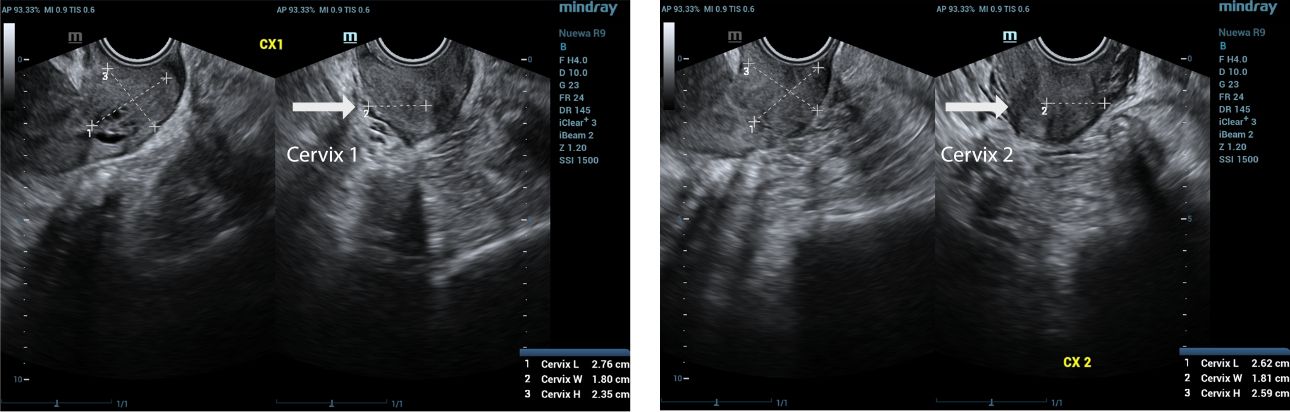

two endocervical cavities noted

There are two endocervical cavities noted

During the ultrasound examination, we observed a normal vagina and two cervixes. On the transverse view, two distinct endometrial echoes were visualized, raising suspicion for a possible congenital uterine anomaly such as a septate or bicornuate uterus.